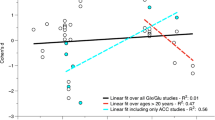

Correlations between altered metabolite ratios and intellectual quotient and autism diagnostic scores

In the insula, the tNAA/tCr was negatively correlated with verbal IQ (r = − 0.474, p = 0.026) in the ASD group and with performance IQ in TD controls (rs =− 0.465, p = 0.029). In the hippocampus, we did find a negative correlation between the total scores of ADOS and Glx ratios (Glx/tCr: r = − 0.564, p = 0.012; replicated for Glx/tCho: r = − 0.595, p = 0.007) in the ASD group. We also found a correlation of tNAA/tCho measures between the putamen and insula: rs = 0.717, p < 0.001.

It is important to uncover links between brain metabolites and ASD symptomatology and cognition51,54,61,64. Therefore, we investigated in an exploratory manner correlations between altered metabolite ratios and clinical and diagnostic measures (IQ, ADOS and ADI-R). In the insula, a weak negative correlation was found between tNAA/tCr and IQ measures (verbal subscale in ASD and performance IQ in the control group). In the hippocampus there was a moderate negative correlation between Glx ratios in the ASD group and total score of ADOS. The observed correlation of tNAA/tCho measures between the putamen and insula suggests that pathology in both structures may be associated. Given that it is known that these structures are strongly associated from the anatomical and functional points of view, this motivates future studies to investigate this relationship.